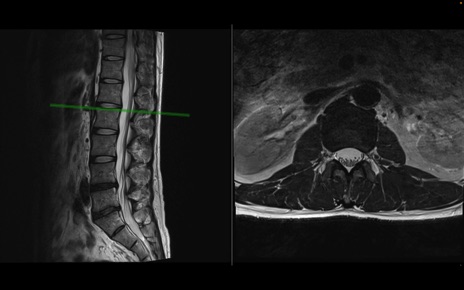

【整形】TIPS症例1 腰椎MRI 横断像と矢状断像

【症例】40歳代男性

【主訴】左臀部〜大腿後面痛み

【現病歴】2週間前から腰痛あり。2日前に夜中にくしゃみをした際に激痛が出現。疼痛強いため来院。

【身体所見】左臀部〜大腿後面、下腿後面のしびれ。SLR -/+ 30度、うつ伏せ困難、筋力低下なし。

異常所見と診断は?